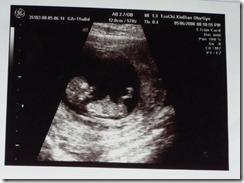

當醫生一來,一樣又是拿著探棒往Annie的肚子上左右掃描,不過……這次掃出來的不再是隻小蛔蟲了!

這次一掃…竟然掃出了一個人形,然後他就手腳縮起來躺在那邊,醫生還開了聲納,讓我們聽聽他的心跳...當時我又傻眼了,怎麼才一個月,就變的那麼大,而且心跳好大聲喔!!

而且他還跳了一下,不知道是不是知道他的爸媽正在看他,所以要秀一下給我們看,不過....不要後空翻就好